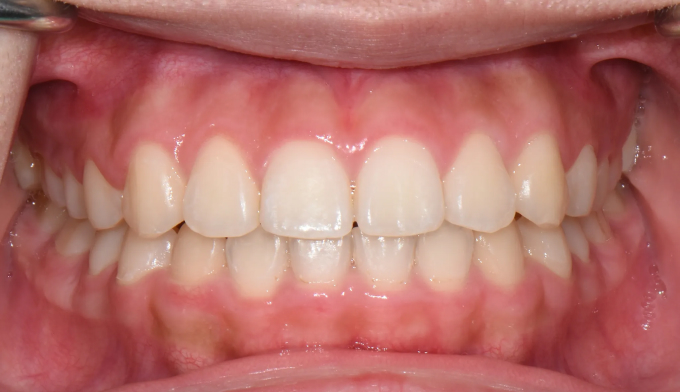

덧니

심하지 않은 덧니의 경우에는 교정기간이 비교적 짧습니다.

총 교정기간은 13개월입니다.